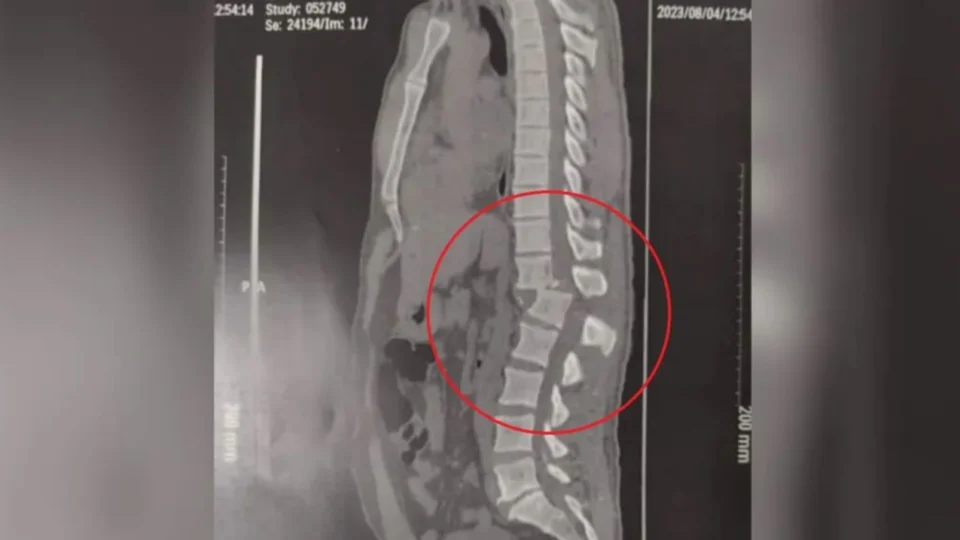

Após sofrer acidente em academia no Ceará, Regilâneo da Silva Inácio, de 42 anos, teve a coluna descolada e tem 1% de chance de voltar a andar.

Um exame de tomografia da coluna do paciente foi divulgado pela família, nesta segunda-feira (7).

Na imagem, é possível ver a gravíssima lesão, conforme os médicos, ocasionada por acidente com a máquina “hack squat”, usada para fazer agachamento.

No último sábado (5), o homem passou por cirurgia de cerca de quatro horas que consistiu na inclusão de pinos e parafusos para reduzir a fratura na coluna.

A lesão ocorreu na região toracolombar e, segundo o profissional, e provocou a danificação de neurônios.